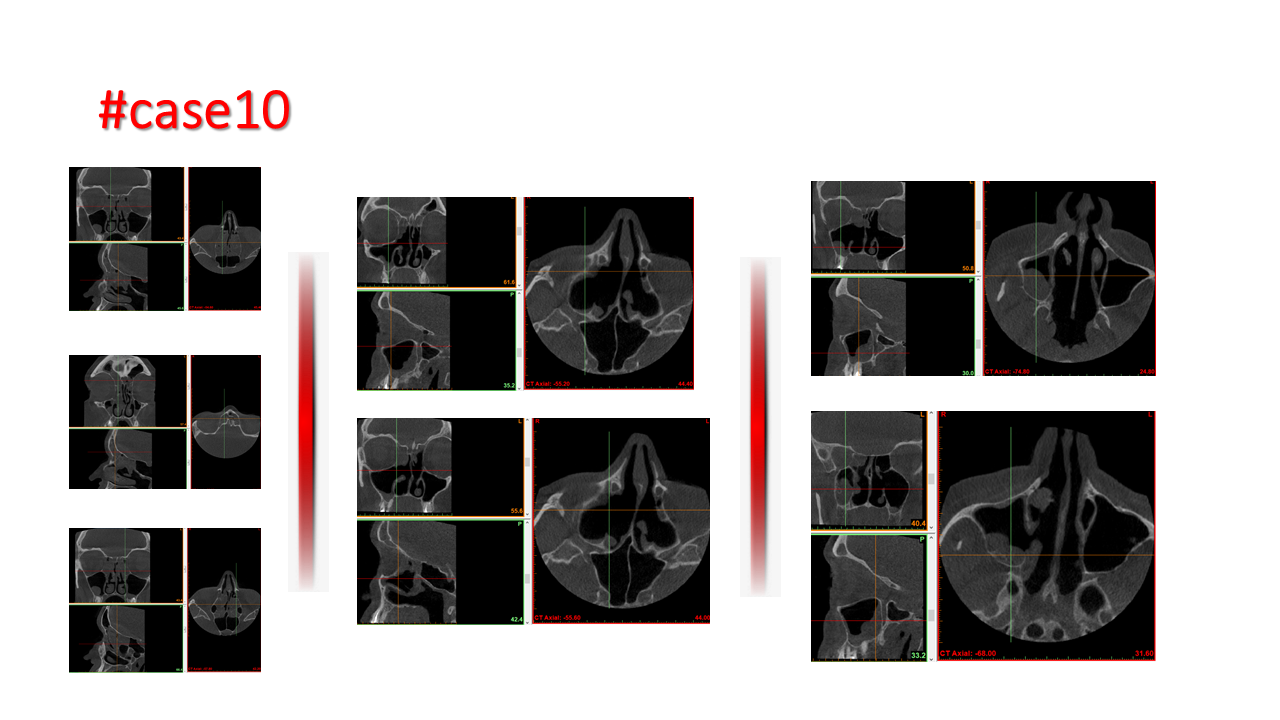

FESS Case Review and Radiologic Analysis (30.09.2016)

Case-based presentation focused on pre- and postoperative imaging in functional endoscopic sinus surgery (FESS). Includes anatomical landmarks, surgical variations, sinus pathology, and technique evaluation. Delivered by Dr. Levon Galstyan at AAOMFS.